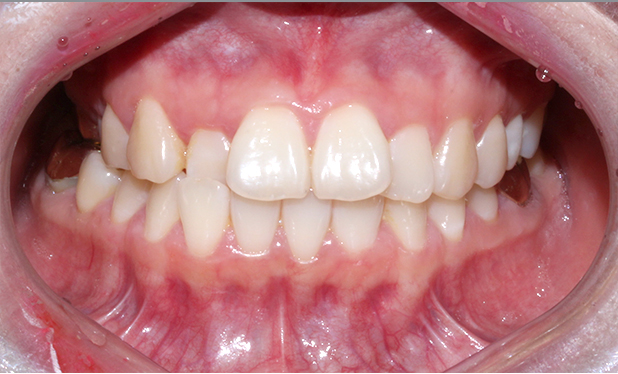

[4개월 교정이 끝난 모습]

4개월만에 가지런하게

치열이 바뀐 모습입니다.

생각보다 더 빠르게

교정이 끝났는데요 ^_^

치아 모양도 고르고 예쁘게

잘 교정되었습니다.

전체 교정만큼 고생하지 않고

빠른 기간동안 개선되어

환자분도 굉장히 만족하셨습니다.

하지만 치아는

늘 제자리로 돌아가려는

성질이 있기 때문에

유지장치를 잘 해주셔야

가지런한 치아를

오랫동안 유지할 수 있습니다 :)